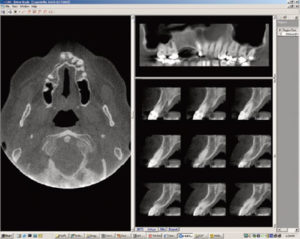

Here's where 3-D imaging is invaluable. It lets dentists see patients' anatomies in all dimensions by creating a 360° analysis. These images give dental professionals a complete makeup of the human jaw, face, and associated structures-something unattainable in 2-D imaging.

In fact, Cone Beam technology is specifically designed to capture human oral and maxillofacial features. It provides a linear path to treatment by taking a complete 3-D scan of the face and displaying the images on an accompanying computer screen within minutes. This gives operators the ability to reconstruct the data in a very short period of time, and analyze the complete surface.

The scanner uses a cone shaped X-ray beam rather than a conventional linear fan beam to obtain images of the bony structures of the skull. Cone Beam systems use a square 2-D array of detectors to capture the cone shaped beam providing a volume of data for dental specialists.

The 3-D scan also exposes issues previously undetectable with traditional methods, giving dental professionals better insight into the relationship between patients' underlying dental structures and soft tissue. Such detailed information greatly increases the accuracy, precision, and efficiency of their patient diagnosis and treatment.